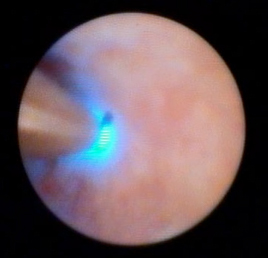

Confocal endomicroscopy image of duct tissue

Confocal imaging may be used to visualize the pancreatic duct.